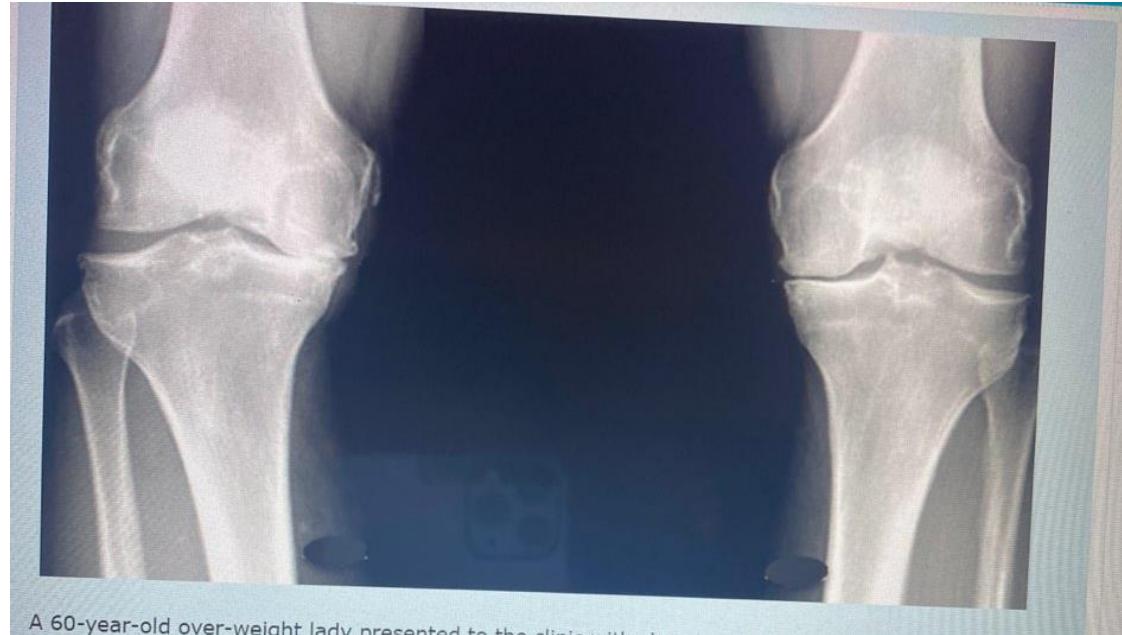

A 60-year-old overweight lady presented to clinic with chronic pain in both knees. A standing AP x-ray of both knees is shown.

Q1: Mention TWO findings on this X-ray

- Narrowing of the joint space

- Osteophytes

Q2: What is the diagnosis?

- Bilateral knee osteoarthritis